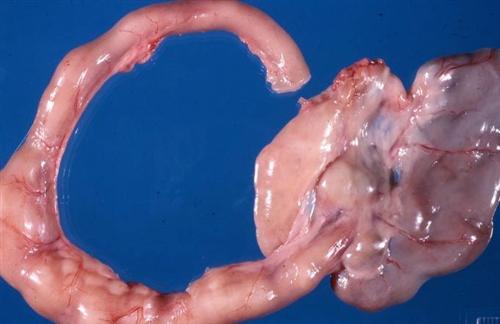

相关图片